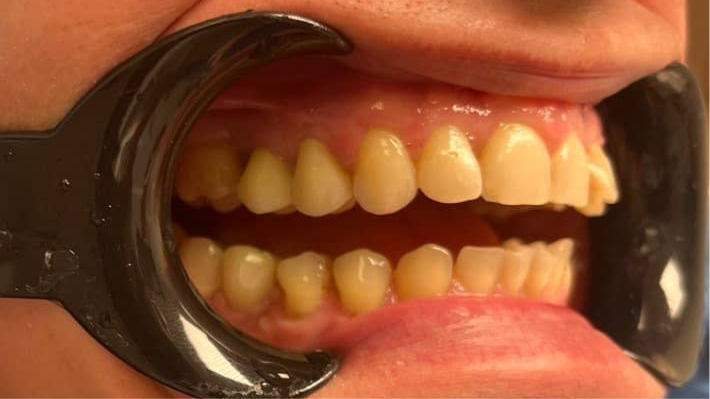

Сильное разрушение двух жевательных зубов:

как циркониевые коронки устранили травму слизистой и вернули возможность нормально жевать

До

Клиническая ситуация

Пациент обратился в стоматологию «Забота» со следующими жалобами:

• постоянная травма щеки и слизистой острыми остатками разрушенных жевательных зубов

(отмечались болезненные язвочки и эрозии на внутренней поверхности щеки);

• невозможность нормально пережёвывать пищу — пациент избегал нагрузки на сторону с разрушенными зубами;

• боль при надкусывании даже мягкой пищи;

• психологический дискомфорт и страх, что зубы придётся удалять.

Анамнез: два жевательных зуба длительное время не лечились. Первоначальный кариес перешёл в глубокое разрушение коронковой части. Обращение к стоматологу откладывалось годами из‑за страха боли и финансовых ограничений.

В результате клинического осмотра и рентгенологического исследования установлено:

Параметр

Выявленная патология

Степень разрушения

Более 50% коронковой части каждого зуба

Состояние краёв зуба

Острые, неровные сколы, травмирующие мягкие ткани

Жизнеспособность пульпы

Зубы депульпированы

Состояние корней

Корни сохранны, периапикальных изменений нет

(зубы можно сохранить)

Жевательная нагрузка

Резкое снижение, жевание преимущественно

на противоположной стороне